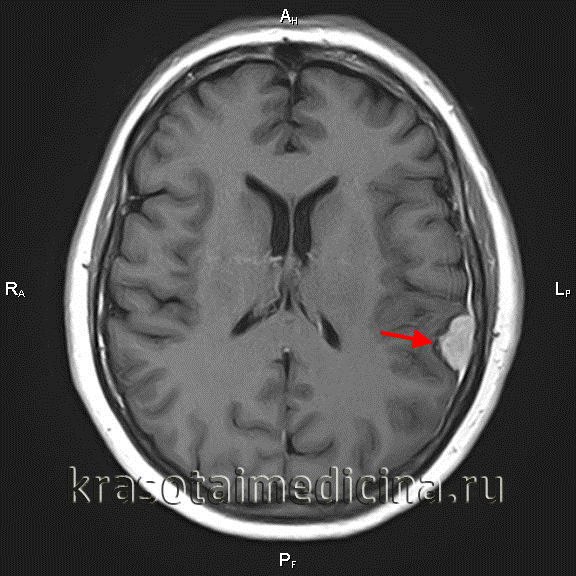

Назначение томографических методов исследования является обязательным при диагностике менингиом. МРТ головного мозга позволяет определить наличие объемного образования. Сплоченность опухоли с твердой мозговой оболочкой помогает визуализировать состояние окружающей ткани. Сигнал МРТ в режиме Т1 напоминает сигнал от мозга, в режиме Т2 обнаруживается гиперинтенсивный сигнал и отек мозга. МРТ можно использовать во время операции для мониторинга удаления всех опухолей и получения материала для гистологического исследования. МР-спектроскопия используется для определения химического профиля опухоли.